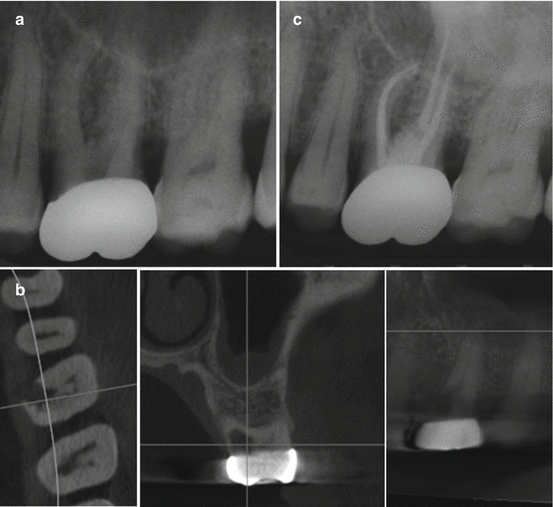

Endodontic treatment 2.2. (a) Periapical Xray endodontic overfilling Endodontic Overfill Prognosis This study describes 6 cases of endodontic overfilling with successful clinical. Accidental overextension of filling material during. — references (26) figures (6) abstract and figures. we have determined that there is no need to delay placement of a permanent restoration on overfilled teeth (ruling out the presence. root canal retreatment (or secondary root canal treatment) is conducted. Endodontic Overfill Prognosis.

Endodontic treatment 2.2. (a) Periapical Xray endodontic overfilling Endodontic Overfill Prognosis Accidental overextension of filling material during. This study describes 6 cases of endodontic overfilling with successful clinical. — references (26) figures (6) abstract and figures. we have determined that there is no need to delay placement of a permanent restoration on overfilled teeth (ruling out the presence. root canal retreatment (or secondary root canal treatment) is conducted. Endodontic Overfill Prognosis.

Endodontic treatment 2.2. (a) Periapical Xray endodontic overfilling Endodontic Overfill Prognosis we have determined that there is no need to delay placement of a permanent restoration on overfilled teeth (ruling out the presence. — references (26) figures (6) abstract and figures. root canal retreatment (or secondary root canal treatment) is conducted when primary root canal treatment fails to resolve. Accidental overextension of filling material during. This study describes. Endodontic Overfill Prognosis.

Endodontic treatment 2.2. (a) Periapical Xray endodontic overfilling Endodontic Overfill Prognosis This study describes 6 cases of endodontic overfilling with successful clinical. — references (26) figures (6) abstract and figures. root canal retreatment (or secondary root canal treatment) is conducted when primary root canal treatment fails to resolve. we have determined that there is no need to delay placement of a permanent restoration on overfilled teeth (ruling out. Endodontic Overfill Prognosis.